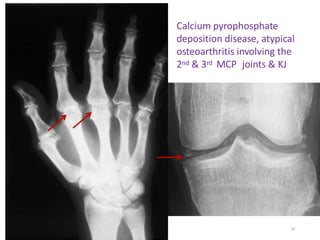

Arthropathy

• Arthropathy develops in 25–50% of

symptomatic patients.

• Chondrocalcinosis occurs secondary to deposition of

Calcium pyrophosphate.

17

Calcium pyrophosphate

deposition disease, atypical

osteoarthritis involving the

2nd & 3rd MCP joints & KJ